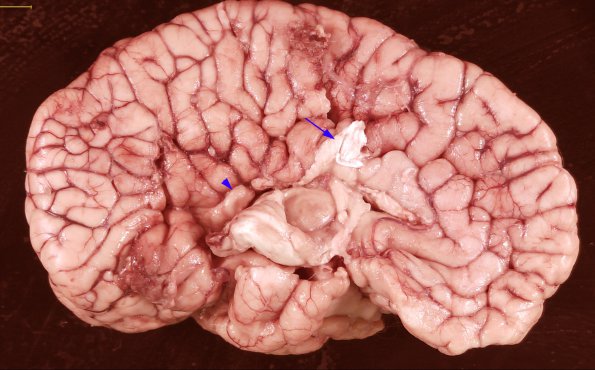

In this brain an Arnold-Chiari malformation (not shown) is associated with nearly complete agenesis of the corpus callosum (residual callosum, arrow) which has resulted in replacement of the cingulate gyrus with radial gyri (arrowhead)